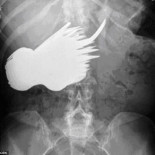

La tan buscada solución a la adicción a la cocaína podría estar en una bacteria. Una enzima bacteriana, la cocaína esterasa (CocE) ha logrado reducir la necesidad de cocaína en ratas adictas. Los investigadores desarrollaron una nueva versión de la enzima, con una doble mutación y administraron la sustancia (DM CocE) a un grupo de ratas de laboratorio.